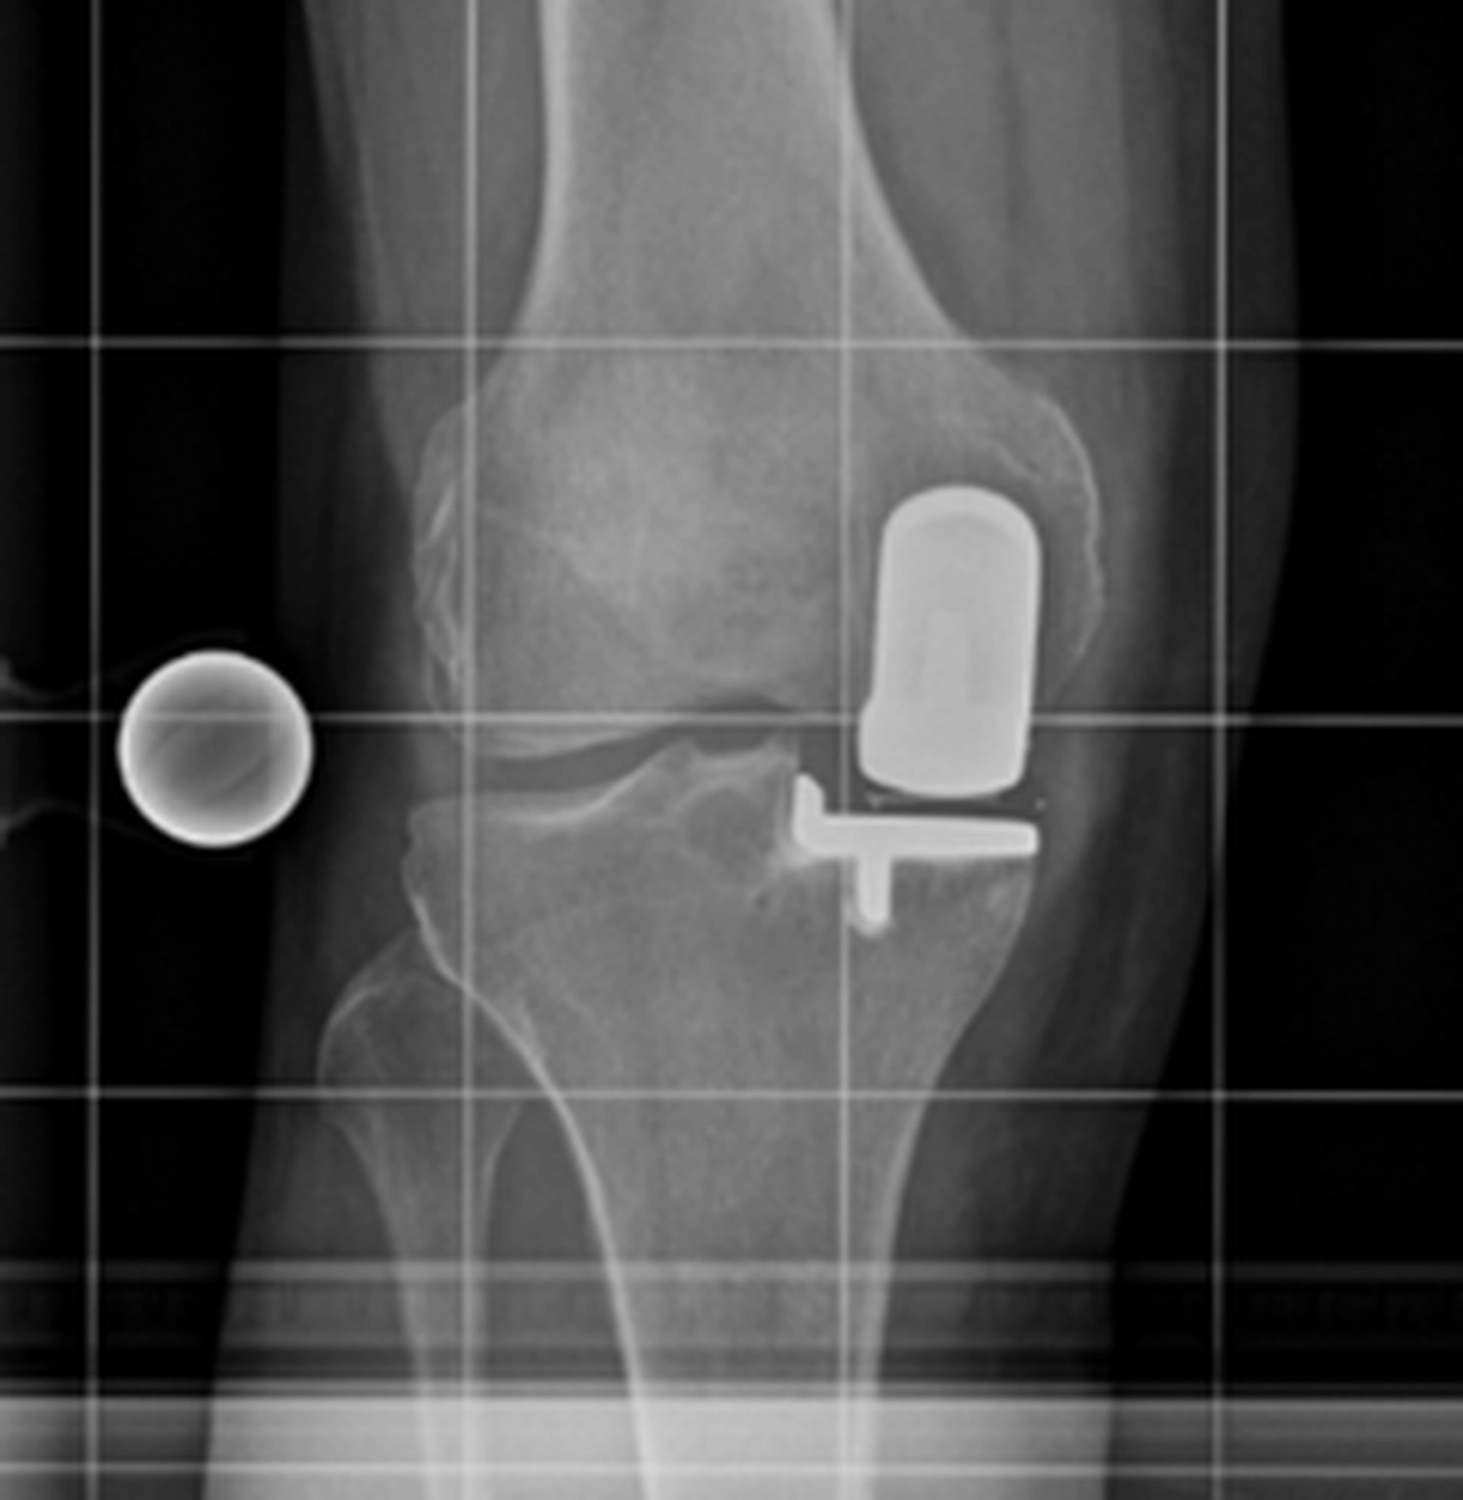

Bei der Implantation einer Knieprothese werden die zerstörten Gelenkflächen des Oberschenkel- und Schienbeinknochens millimetergenau entfernt und durch passgenaue Metallkomponenten ersetzt.

Dazwischen liegt ein hochbelastbares Kunststoffinlay, das die Gleitfläche bildet.

Je nach Schädigung und Gelenkzustand werden unterschiedliche Prothesenarten verwendet:

Die Operation dauert etwa 60 bis 90 Minuten und erfolgt unter Voll- oder Spinalanästhesie.